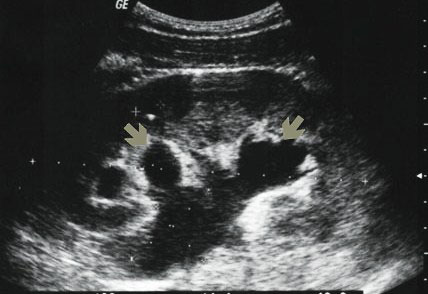

Cлияние расширенных чашечек с расширенной лоханкой! Гидронефроз?

- ren.jpg (25.87 КБ) 5699 просмотров

Да, отличный пример!